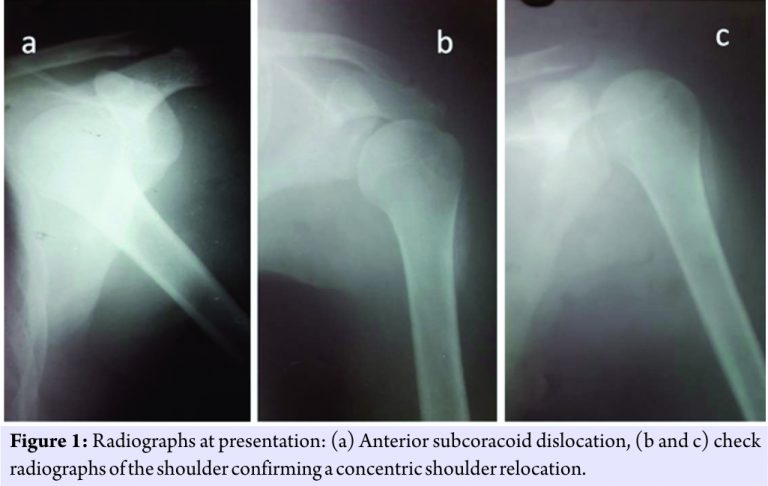

We report a case of a 24-year-old male with a left-sided anterior subcoracoid shoulder dislocation (Fig. 1a) following a road traffic accident. This was the first episode of dislocation. The shoulder was closed reduced by the Kocher’s technique within 3 hours of trauma, and a post-reduction radiograph was taken to confirm concentric reduction. The shoulder was immobilized for 3 weeks (Fig. 1b and c), following which rotator cuff strengthening exercises were initiated. The patient was followed up, after the shoulder was reduced at 3 weeks, 3 months, and 6 months, and then, the patient reported after 2 years. This patient was a non-alcoholic healthy college-going student who was not on any medications. At 6-month follow-up, the left shoulder radiograph showed a sclerotic sector of the head with cortical erosions near the greater tuberosity (Fig. 2a and b).